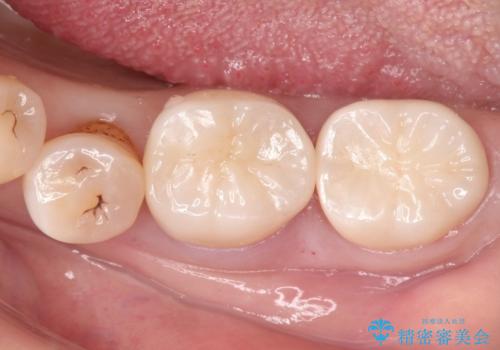

咬合が強く、歯牙にマイクロクラックが入っている状態でした。歯髄は保存可能と診断され、フルジルコニアクラウンによる治療を行いました。

咬合面に広範囲の修復物がある状態で中心に強い力が加わると歯牙は外方性の歪みが生じ、マイクロクラックができます。これを防ぐには、咬頭被覆するアンレー、もしくはクラウンによる治療が必要です。